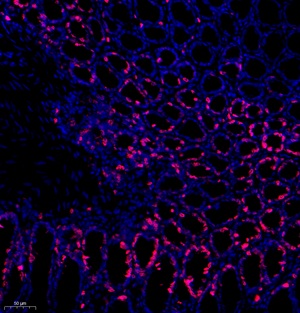

| IF analysis of ki67 (GB111141). Sample: Rat colon (Paraffin), 4% PFA (G1101) 12-24h. Antigen retrieval: TE buffer (pH 9.0) (G1203),98°C,20min. Blocking buffer: 3% BSA in PBS (GC305010), RT, 30min. Primary antibody: 1: 600, 4°C overnight. Secondary antibody: Cy3 conjugated Goat Anti-Rabbit IgG (H+L) (GB21303), 1: 300 RT, 1h. |